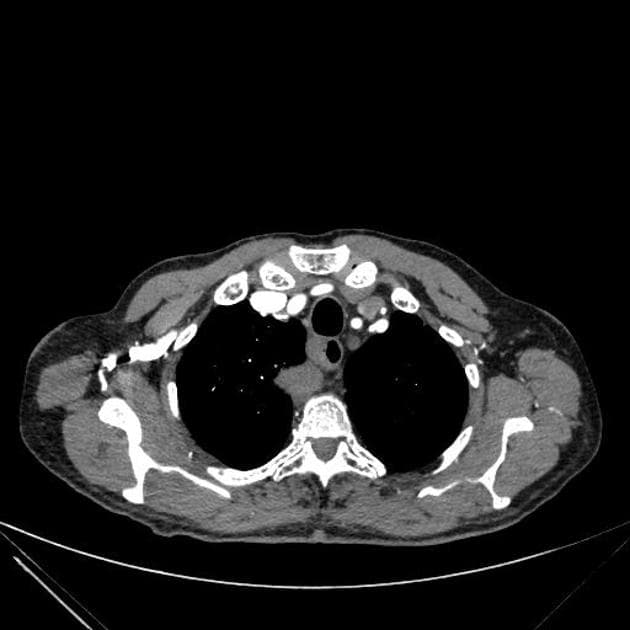

- Thấy vạt bóc tách (flap) trong động mạch chủ (aorta), xuất phát ở đoạn động mạch chủ lên (ascending aorta) ngay phía dưới gốc động mạch chủ (aortic root), xoắn dọc theo toàn bộ động mạch chủ (aorta), tạo thành buồng giả (false lumen) lớn nằm chủ yếu phía sau và chèn ép buồng thật (true lumen), buồng thật có hình bầu dục trên mặt cắt ngang.

- Thấy các cửa sổ thông (fenestration) tại đoạn cung động mạch chủ (aortic arch) gần đoạn gần và ngay trước phân nhánh động mạch chủ (aortic bifurcation).

- Toàn bộ động mạch chủ (aorta) giãn, đường kính lớn nhất tại đoạn động mạch chủ xuống ngực (descending thoracic aorta) đo được 5,1 cm.

- Buồng giả (false lumen) có hiện tượng huyết khối thành mạch (mural thrombus) một phần, không đồng đều, dày nhất ở đoạn động mạch chủ xuống ngực (descending thoracic aorta), làm giảm đường kính lòng mạch khoảng 50%.

- Thân tạng (coeliac trunk), động mạch mạc treo tràng trên (mesenteric artery) và cả hai động mạch thận (renal arteries) đều xuất phát từ buồng thật (true lumen); các động mạch thận (renal arteries) có vẻ tản rộng do động mạch chủ (aorta) giãn và dịch chuyển.

Trường hợp này minh họa một ví dụ điển hình của bóc tách động mạch chủ loại Stanford A / DeBakey I, đặc trưng bởi vết rách nội mạc ở đoạn động mạch chủ lên, lan theo vạt bóc tách dọc cung động mạch chủ và động mạch chủ xuống đến động mạch chủ bụng và động mạch chậu chung. Loại bóc tách này đe dọa tính mạng do nguy cơ chèn ép tim, hở van động mạch chủ cấp, thiếu máu cơ tim và hội chứng thiếu tưới máu cơ quan. Phẫu thuật cấp cứu là cần thiết để ngăn vỡ mạch và tử vong. Các dấu hiệu hình ảnh như giãn động mạch chủ, vạt bóc tách xoắn, chèn ép buồng thật và huyết khối một phần buồng giả giúp chẩn đoán. Việc phân biệt với huyết khối thành động mạch chủ và loét xơ vữa xuyên thành là rất quan trọng vì cách xử trí khác biệt rõ rệt.